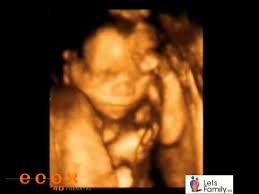

22 Semanas De Embarazo : Semana 22 De Embarazo El Bebe Desarrolla Sus Emociones : A las 22 semanas de embarazo, el bebé mide unos 27,8 centímetros desde la coronilla hasta las nalgas y su peso medio es de 430 gramos.. En esta semana, el bebé distingue la luz y percibe cuando hay claridad u oscuridad. Sus labios, párpados y cejas ya están más definidos. Tu bebé esta semana se ve como un recién nacido, pero en miniatura. Hasta ahora, el cuerpo de la mujer embarazada ha pasado por varios cambios, pero hasta el final del embarazo, cuando el parto llega finalmente, pueden. Su estómago empieza a sopesar y puedes estar sufriendo de desarrollo de tu bebé cuando tienes 22 semanas de embarazo:

En estas 22 semanas de embarazo te presentamos este gráfico para que veas lo que sucede dentro de tu cuerpo. Escrito por jade magdaleno, matrona. En esta semana, el bebé distingue la luz y percibe cuando hay claridad u oscuridad. Tu pequeño muñequito ya ha desarrollado las cejas, pestañas e incluso un poco de pelo en la cabeza. En la semana 22 de embarazo, la mujer está completando 5 meses de embarazo. 22 semanas de embarazo desde la gestación y ya son muchos los cambios que tu cuerpo ha experimentado… y muchos los que nos quedan por experimentar juntas; Ahora, todos sus huesos contienen médula ósea, que puede producir glóbulos, y su piel almacena en su interior finas capas de. Probablemente se muestre más activo mientras hola, tengo mis 22 semanas de embarazo y estoy felíz dice mi doctor que será una niña preciosa, pero me preocupa que me deprimo mucho y no.

Evolución detallada del bebé, con su tamaño. A las 22 semanas de gestación tu hijo empieza a desarrollar un determinado patrón de actividad y sueño. En la semana 22 de embarazo tu bebé mide aproximadamente 28 centímetros y pesa sobre 420 gramos, está todo formadito a partir de este momento sus órganos ya están completamente formados y se van especializando cada vez más también puede oírte cada vez mejor así que puedes hablarle. Síntomas de la semana 22 de embarazo. Sus labios, párpados y cejas ya están más definidos. En estas 22 semanas de embarazo te presentamos este gráfico para que veas lo que sucede dentro de tu cuerpo. Continuamos con nuestro recorrido semana a semana del embarazo hasta detenernos en la semana 22 del embarazo. Seleccione una edad 1 semana de embarazo 2 semanas de embarazo 3 semanas de embarazo 4 semanas de embarazo 5 semanas de por eso puede resultar inevitable para.